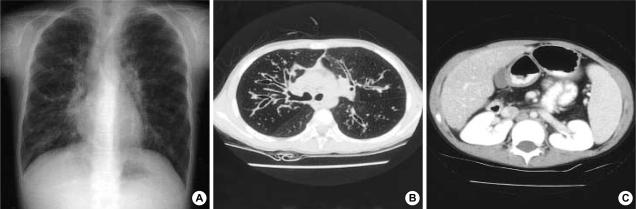

Cystic fibrosis (CF) is inherited as an autosomal recessive trait, and the mutations in cystic fibrosis transmembrane conductance regulator (CFTR) gene contributes to the CF syndrome. Although CF is common in Caucasians, it is known to be rare in Asians. Recently, we experienced two cases of CF in Korean children. The patients were girls with chronic productive cough since early infancy. Chest computed tomography showed the diffuse bronchiectasis in both lungs, and their diagnosis was confirmed by the repeated analysis of a quantitative pilocarpine iontophoresis test (QPIT). The sweat chloride concentrations of the first patient were 108.1 mM/L and 96.7 mM/L. The genetic analysis revealed that she was the compound heterozygote of Q1291X and IVS8 T5-M470V. In the second case, the sweat chloride concentrations were 95.0 mM/L and 77.5 mM/L. Although we performed a comprehensive search for the coding regions and exon-intron splicing junctions of CFTR gene, no obvious disease-related mutations were detected in the second case. To our knowledge, this is the first report of CF in Korean children identified by a QPIT and genetic analysis. The possibility of CF should be suspected in those patients with chronic respiratory symptoms even in Korea.

囊性纤维化(CF)以常染色体隐性性状遗传,囊性纤维化跨膜传导调节因子(CFTR)基因突变导致CF综合征。虽然CF在白种人中很常见,但在亚洲人中却很罕见。最近,我们在韩国儿童中遇到了两例CF病例。患者为女童,自婴儿早期起就有慢性咳痰。胸部计算机断层扫描显示双肺弥漫性支气管扩张,通过重复进行定量毛果芸香碱离子透入试验(QPIT)分析确诊。首例患者的汗液氯化物浓度分别为108.1 mM/L和96.7 mM/L。基因分析显示她是Q1291X和IVS8 T5-M470V的复合杂合子。第二例患者的汗液氯化物浓度分别为95.0 mM/L和77.5 mM/L。尽管我们对CFTR基因的编码区和外显子-内含子剪接连接进行了全面搜索,但在第二例中未检测到明显的疾病相关突变。据我们所知,这是韩国儿童中通过QPIT和基因分析确诊CF的首例报告。即使在韩国,对于有慢性呼吸道症状的患者也应怀疑CF的可能性。